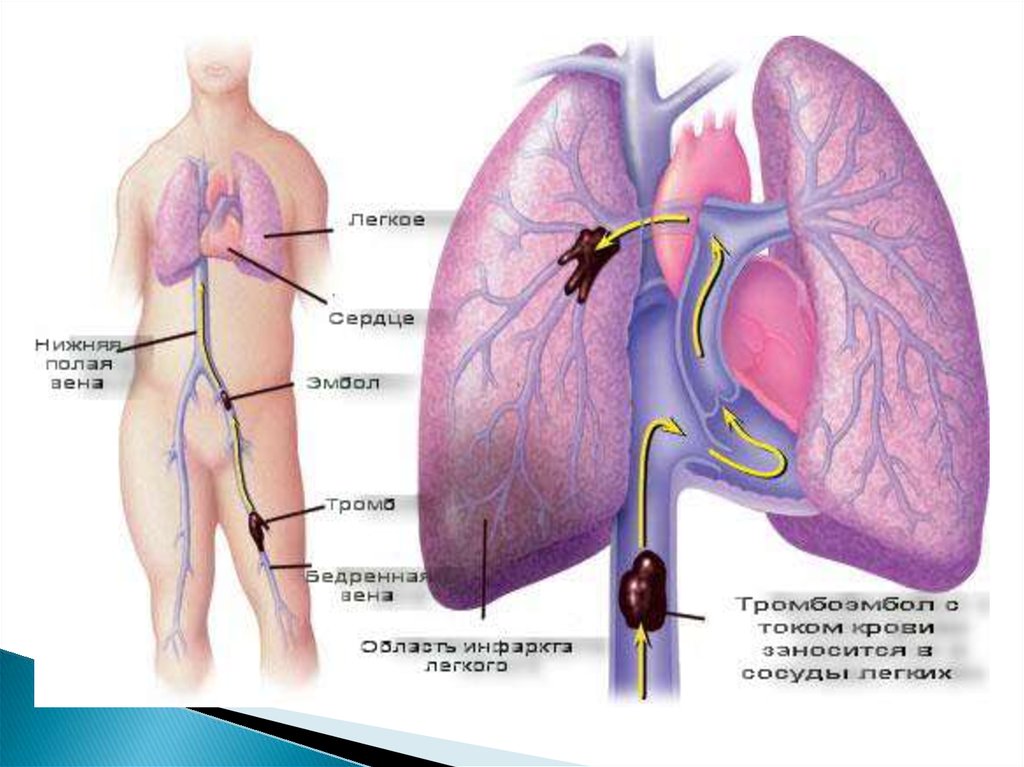

Симптомы и причины скопления воды в легких

Раздел: Ракурсы просвещения